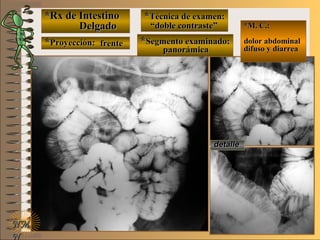

*Rx de Estómago*Rx de Estómago

**Proyección:Proyección:

**Técnica de examen:Técnica de examen:

A-A-

B-B-

C-C-